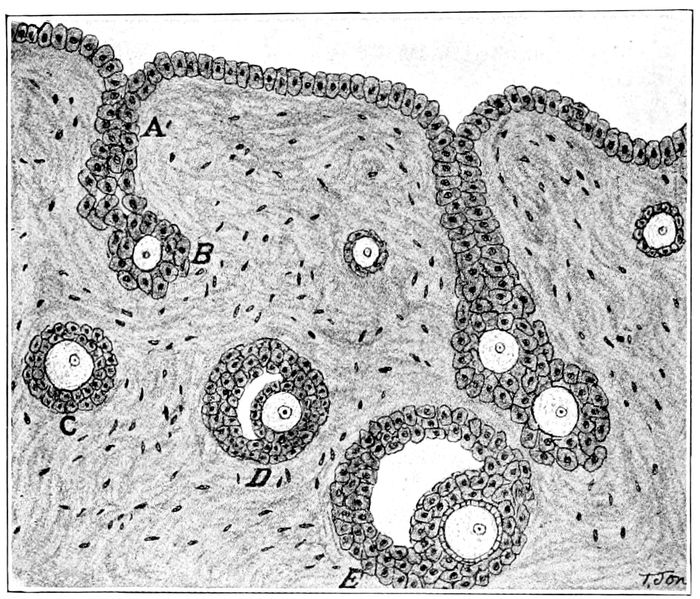

Fig. 12.—Development of the ovary (after Wiedersheim). A, an ingrowth of the germinal epithelium, forming a cell-cord, which breaks up into primitive Graafian follicles; B, a primitive Graafian follicle, with its contained primitive ovum; C, D, E, later stages in the development of the Graafian follicle. (Crossen.)

Ovulation.—Ovulation is the process whereby the eggs

are discharged from the Graafian follicle which matures

and protects them in the ovary. The egg is a true cell

Fig. 13.—Graafian follicles. One contains two ovules which, if fertilized, will produce twins. If all three ovules are fertilized, triplets will result. (Bumm.)